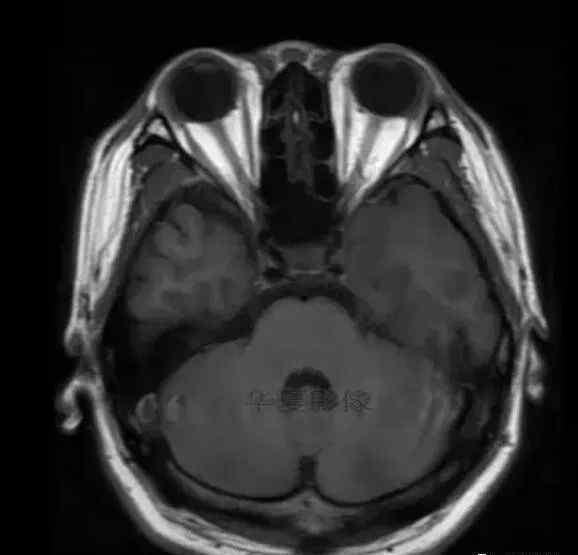

1.左侧颞叶、海马和岛叶T1WI信号低,T2WI信号高

2.病变没有明显的边界

3.占用效果不明显